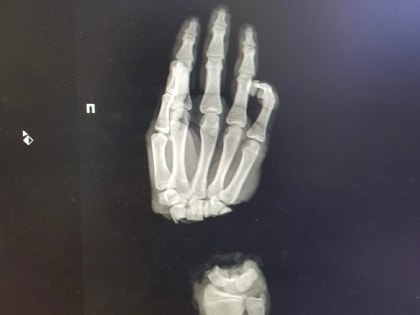

Нижегородские врачи спасли руку 16-летнему подростку

16-летний парень из Владимирской области оказался в нижегородском медучреждении, после того как случайно отрубил себе руку.

Нижегородские медики пришили подростку из Коврова отрубленную руку

Нижегородские медики пришили кисть подростку из Коврова. Юноша поступил в ПИМУ со страшной травмой: он отрубил себе руку, когда колол дрова.

Нижегородские хирурги пришили подростку отрубленную топором кисть

Врачи Университетской клиники ПИМУ пришили подростку отрубленную кисть. Об этом рассказал глава вуза Николай Карякин в соцсетях.